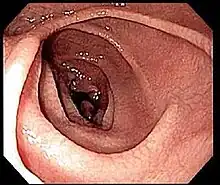

Endoscopic still of duodenum of a person with coeliac disease showing scalloping of folds and "cracked-mud" appearance to mucosa

An upper endoscopy with biopsy of the duodenum (beyond the duodenal bulb) or jejunum is performed to obtain multiple samples (four to eight) from the duodenum. Not all areas may be equally affected; if biopsies are taken from healthy bowel tissue, the result would be a false negative.[40] Even in the same bioptic fragment, different degrees of damage may be present.[16]

Most people with coeliac disease have a small intestine that appears to be normal on endoscopy before the biopsies are examined. However, five findings have been associated with high specificity for coeliac disease: scalloping of the small bowel folds (pictured), paucity in the folds, a mosaic pattern to the mucosa (described as a "cracked-mud" appearance), prominence of the submucosa blood vessels, and a nodular pattern to the mucosa.[96]